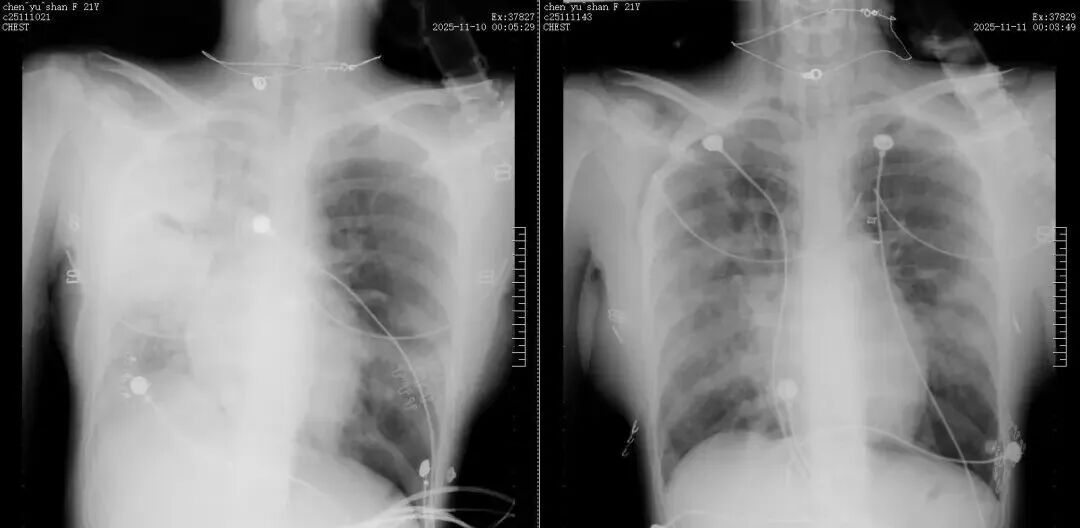

11月11日清晨,赵考昌教授和汤贵良医生查房时,发现小陈在联合呼吸支持下指脉氧饱和度已回升至98%。在评估其身体状态可耐受检查后,团队立即安排床旁支气管镜肺泡灌洗液病原菌检测,精准检出金黄色葡萄球菌、星座链球菌及甲型流感病毒H3N2。明确病因后,医护团队第一时间优化抗生素方案,开展靶向抗感染治疗。当日复查胸片显示,小陈右肺感染较前明显好转,病情迎来重要转机。

治疗前后对比:由此前的“白肺”明显好转